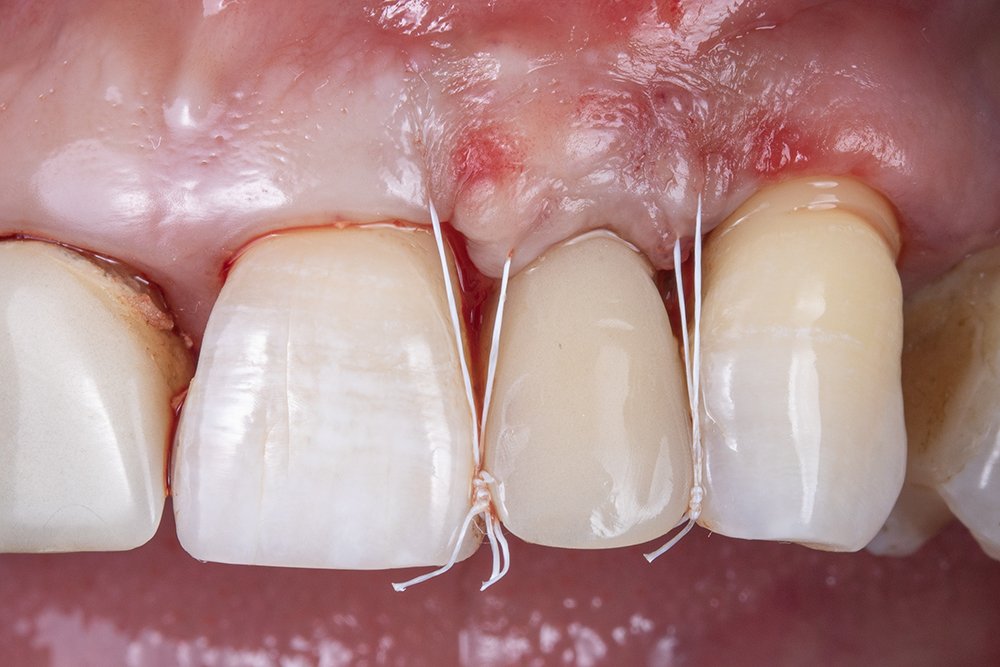

Neste caso, foi realizado um provisório imediato, considerando sua importância para a cicatrização tecidual e definição do perfil de emergência.

Com o provisório instalado, a sutura suspensória foi realizada com o fio de PTFE 5.0 Cytoplast, promovendo um conforto maior para o paciente, pois não há o tensionamento das bordas dos tecidos.

Após o procedimento cirúrgico, a paciente foi orientada sobre todos os cuidados pós-operatórios necessários a serem tomado e a aguardar o tempo de três meses para realizar a coroa definitiva e dar sequência aos outros procedimentos reabilitadores.